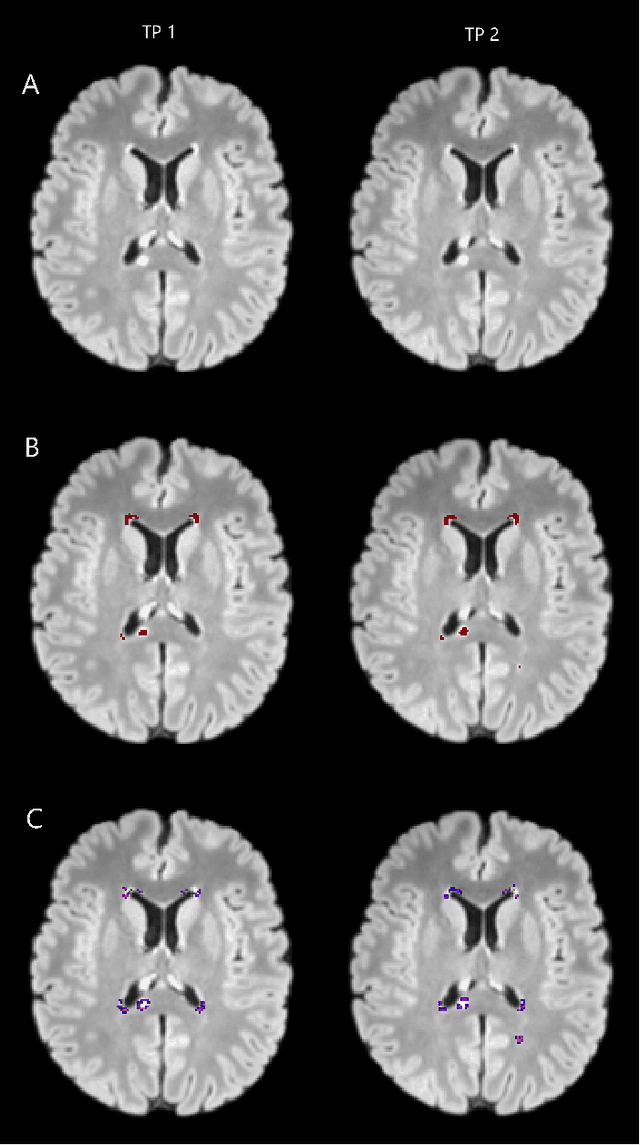

Abstract:Segmentation of both white matter lesions and deep grey matter structures is an important task in the quantification of magnetic resonance imaging in multiple sclerosis. Typically these tasks are performed separately: in this paper we present a single CNN-based segmentation solution for providing fast, reliable segmentations of multimodal MR imagies into lesion classes and healthy-appearing grey- and white-matter structures. We show substantial, statistically significant improvements in both Dice coefficient and in lesion-wise specificity and sensitivity, compared to previous approaches, and agreement with individual human raters in the range of human inter-rater variability. The method is trained on data gathered from a single centre: nonetheless, it performs well on data from centres, scanners and field-strengths not represented in the training dataset. A retrospective study found that the classifier successfully identified lesions missed by the human raters. Lesion labels were provided by human raters, while weak labels for other brain structures (including CSF, cortical grey matter, cortical white matter, cerebellum, amygdala, hippocampus, subcortical GM structures and choroid plexus) were provided by Freesurfer 5.3. The segmentations of these structures compared well, not only with Freesurfer 5.3, but also with FSL-First and Freesurfer 6.1.